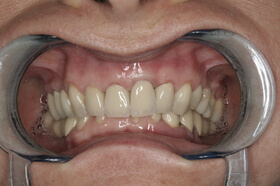

Több, mint tízéves hidak, elkopott fogak. Kezelési terv: a régi hidak cseréje és a többi fog ellátása fém-kerámia koronákkal

Az elkészült fém-kerámia koronák, hidak